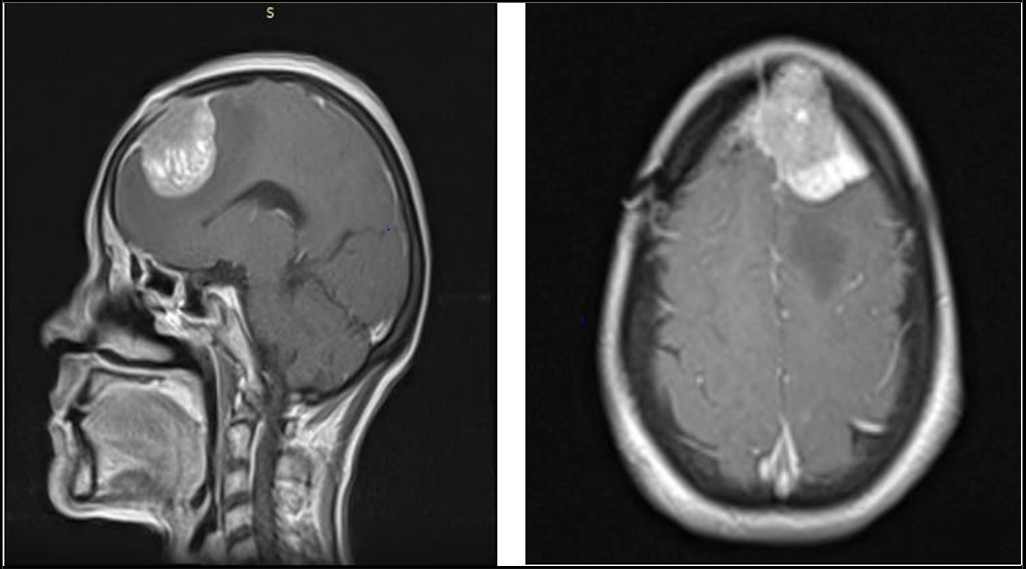

Further imaging with magnetic resonance imaging (MRI) of the brain with and without contrast was performed for surgical planning and staging. The MRI revealed a large, heterogeneously enhancing mass centered in the region of the left ethmoid sinuses, with intracranial extension into the left frontal lobe through a widened cribriform plate as shown in (Figure 1 and 2). Additionally, an enlarged enhancing left cervical level IB lymph node was identified, suggestive of possible regional metastasis. No leptomeningeal or intra- parenchymal post-contrast enhancement was noted.

Figure 1 and 2: Coronal and Axial sections of MRI Brain with contrast showing intracranial extension of olfactory neuroblastoma into left frontal lobe